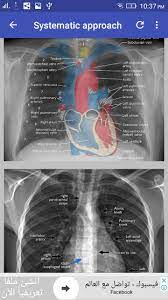

L these two lobes are separated by a major fissure, identical to that seen on the right side, although often slightly more. Dr andrew dixon ◉ and dr jeremy jones ◉ et al. Recognizing normal anatomy on the cxr is key to understanding and interpreting abnormalities. There are many approaches to cxr interpretation, each trying to ensure that key abnormalities are identified and no area is. Vq mismatch and hyponatremia lectures have been popular. Few providers (including mds) are comfortable interpreting their own films. © 2005 adam guttentag, md. Standard frontal chest radiograph (roentgenogram) — upright;

Interpretation of the chest x ray. Chest x ray is probably the most common imaging test. In addition to text and pictures, this tutorial contains interactive features which supplement the text and make it a more dynamic learning. Examination of the chest x ray is a process which requires a systematic approach. Standard frontal chest radiograph (roentgenogram) — upright; Recognizing normal anatomy on the cxr is key to understanding and interpreting abnormalities. Few providers (including mds) are comfortable interpreting their own films. In fact every radiologst should be an expert in chest film reading. Normal heart size is half of the chest width. Generally speaking, a normal cxr should have the lungs looking like zebras in that they are all black with strips. The aim of this study was to investigate the diagnostic accuracy of cxr interpretation by reporting radiographers (technologists). The chest radiograph remains the most important method of chest imaging, providing an easily accessible, inexpensive, quick, and effective diagnostic tool. Learn about chest x ray interpretation with free interactive flashcards.

There are many approaches to cxr interpretation, each trying to ensure that key abnormalities are identified and no area is. Chest x ray basic interpretation by vikram patil 37831 views. These images were saved with anonymous biodata for iom radiology collection and teaching purposes. Chest x ray is probably the most common imaging test. © 2005 adam guttentag, md. Interpretation of the chest x ray. Standard frontal chest radiograph (roentgenogram) — upright; L these two lobes are separated by a major fissure, identical to that seen on the right side, although often slightly more. Examination of the chest x ray is a process which requires a systematic approach. Few providers (including mds) are comfortable interpreting their own films. Generally speaking, a normal cxr should have the lungs looking like zebras in that they are all black with strips. The aim of this study was to investigate the diagnostic accuracy of cxr interpretation by reporting radiographers (technologists). Recognizing normal anatomy on the cxr is key to understanding and interpreting abnormalities.